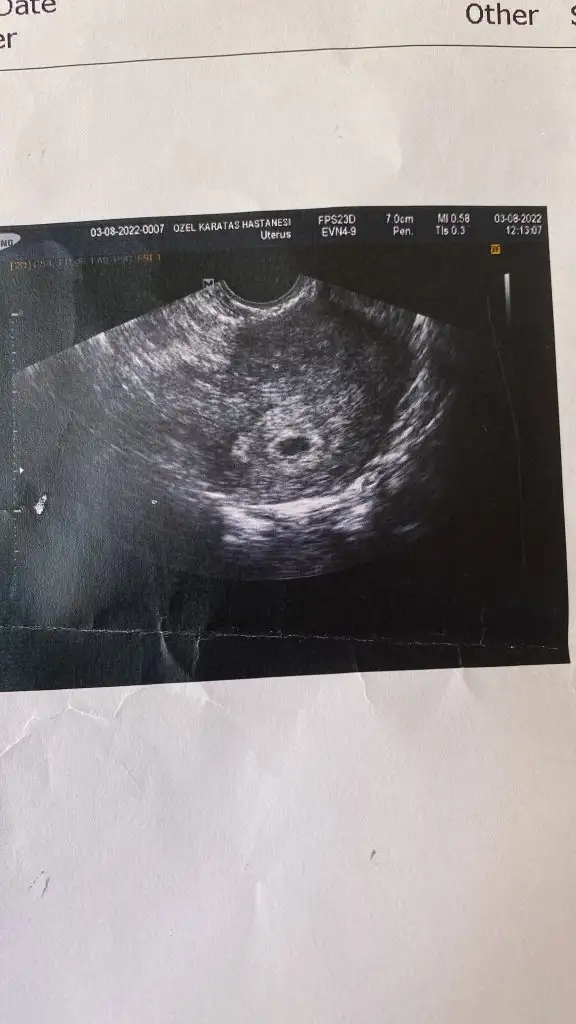

Ultrasonda bebeğin gözüktüğü resmî istiyorsanız yuvarlak değildi 7 haftalık ilken bu şekilde idi